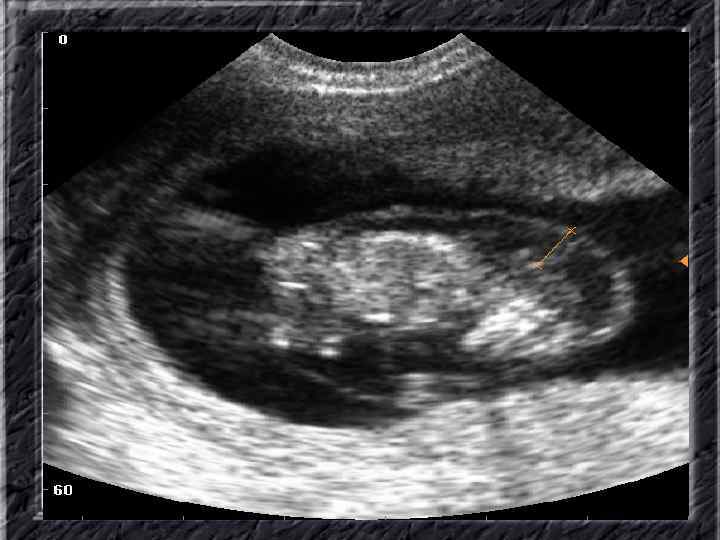

Названия слайдов: • • • Слайд 41. Лапароскопия: эндометриоидная киста яичника. Слайд 42. Лапароскопия: эндометриоидные гетеротопии на поверхности эндометриоидной кисты яичника. Слайд 43. Ультрасонография: поликистозное изменение яичника. Слайд 44. Серозная цистаденома яичника: внешний вид; макропрепарат. Слайд 45. Лапароскопия: цистаденома яичника. Слайд 46. Ультрасонография: папиллярная цистоаденома яичника, содержащая внутри папиллярные разрастания. Слайд 47. Ультраснография: многокамерная киста яичника (муцинозная цистаденома). Слайд 48. Лапароскопия: папиллярная цистаденома. Слайд 49. Ультрасонография: многокамерное жидкостное образование яичника, содержащее полиморфный солидный конгломерат — рак из муцинозной цистаденомы. Слайд 50. Рентгеноконтрастная сальпингография: нормальное наполнение и проходимость обеих маточных труб.

Названия слайдов: • • • • Слайд 61. Лапароскопия: множественные спайки в полости малого таза женщины. Слайд 62. Лапароскопия: признаки спаечной болезни в полости малого таза женщины. Слайд 63. Лапароскопия: деформация маточной трубы при спаечном процессе в полости малого таза. Слайд 64. Ультрасонография: спаечный процесс в малом тазу. Слайд 65. Ультрасонография: мультифолликулярные яичники. Слайд 66. Ультрасонография: кистома яичника. Слайд 67. Ультрасонография: патолоргия эндометрия. Слайд 68. Ультрасонография: внематочная беременность. Слайд 69. Ультрасонография: внематочная беременность. Слайд 70. Кольпоскопия: кандлилома – папиллома. Слайд 71. Кольпоскопия: кандлидозные бели. Слайд 72. Кольпоскопия: полип шейки матки. Слайд 73. Кольпоскопия: эрозия шейки матки. Слайд 74. Кольпоскопия: экспульсия ВМС.